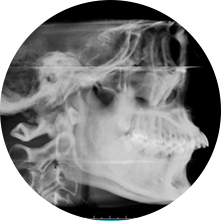

首先,需要拍攝牙齒照片、X光片并進行掃描/取模,一遍據此制定治療方案